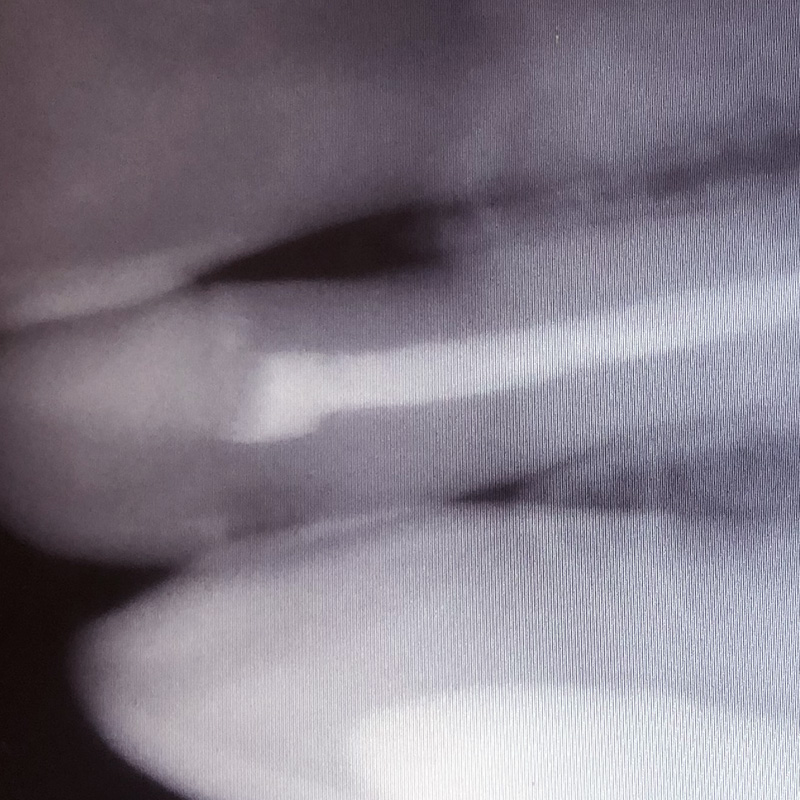

- постоянная пломбировка 3 каналов ;

- рентген-контроль.